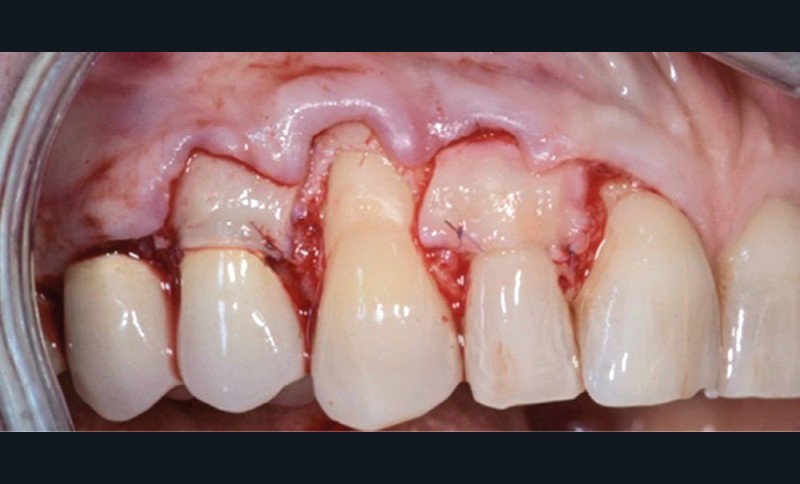

Le lambeau est ensuite décollé grâce à la méthode partielle-totale-partielle (« Split-Full-Split »). Les papilles chirurgicales sont décollées en épaisseur partielle afin d’obtenir un lit receveur et de stabiliser la position du lambeau au moment des sutures. Le lambeau est levé en pleine épaisseur jusqu’à la ligne de jonction muco-gingivale afin d’emporter le périoste, qui permet la vascularisation du lambeau. Enfin, dans un objectif de gain de laxité, le lambeau sera disséqué en demi-épaisseur dans la muqueuse alvéolaire. Cette dissection se fait en deux plans : un plan profond et un plan superficiel parallèle au lambeau muqueux. Le but est de permettre de repositionner le lambeau avec un minimum de tension.